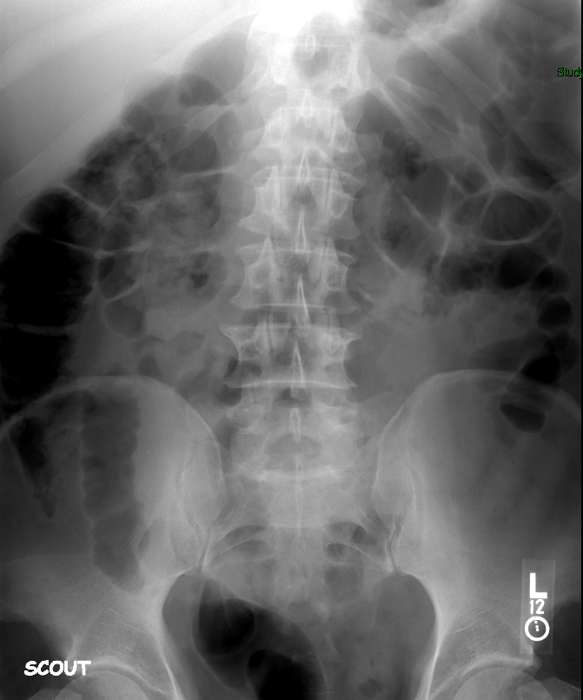

- The technologist will obtain a scout image. Assess the image for any possible contraindications such as pneumoperitoneum, evidence of ileus or obstruction, or residual contrast material

(key image 1).